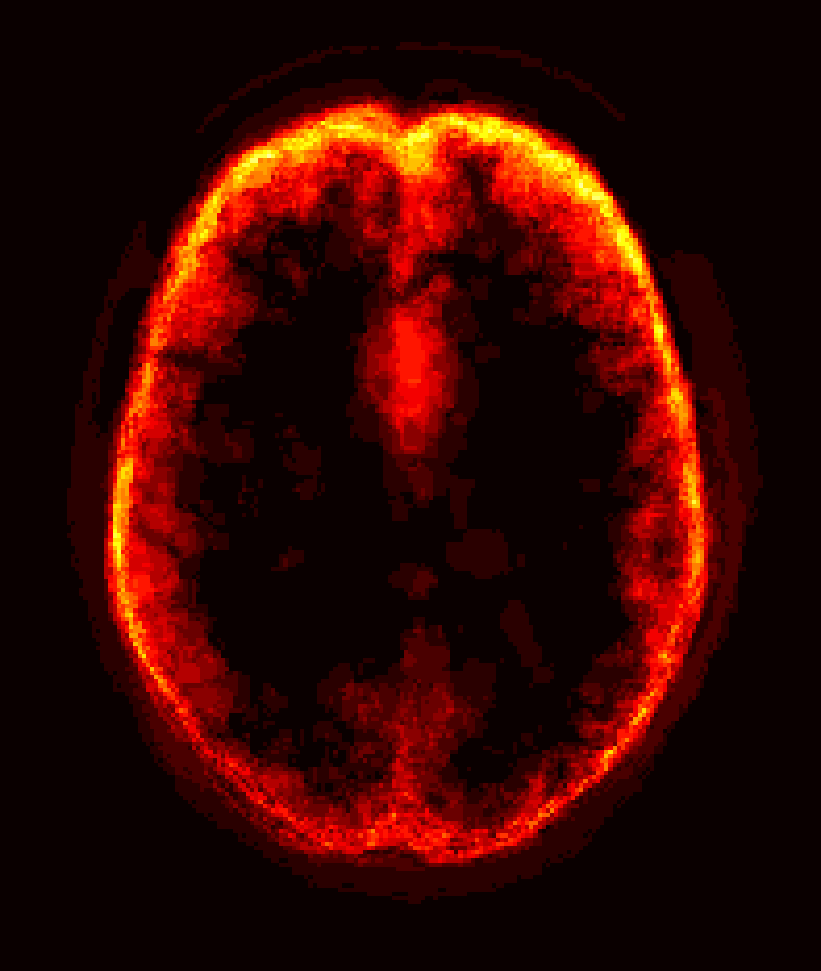

[Uncaptioned image] [Uncaptioned image] [Uncaptioned image] [Uncaptioned image]

(a) (b) (c) (d)

Figure 8: Example BRATS image with its decomposition result in atlas space. (a) Input image after pre-processing; (b) quasi-normal image L+M𝐿𝑀L+M; (c) non-brain image S𝑆S; (d) pathology image T𝑇T.

In addition to extracting the brain from pathological datasets, our method also allows for the estimation of a corresponding quasi-normal image in atlas space, although this is not the main goal of this paper. Fig.8 shows an example of the reconstructed quasi-normal image (L𝐿L) for an image of the BRATS dataset, as well as an estimation of the pathology (pathology image T𝑇T and non-brain image S𝑆S). Compared to the original image, the pathology shown in the quasi-normal image has been greatly reduced. Hence this image can be used for the registration with a normal image or a normal atlas. This has been shown to improve registration accuracy for the registration of pathological images [27]. Furthermore, an estimate of the pathology (here a tumor) is also obtained which may be useful for further analysis. Note that in this example image the total variation term captures more than just the tumor. This may be due to inconsistencies in the image appearance between the normal images (obtained from OASIS data) and the test dataset. As our goal is atlas alignment rather than quasi-normal image reconstruction or pathology segmentation, such a decomposition is acceptable, although we could improve this by tuning the parameters or applying regularization steps as in [27].